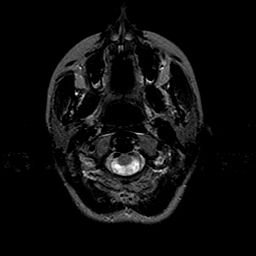

Vascular Malformation:T2-weighted MR #1 -- Slice #0

[Home][Help][Clinical] Slice 0